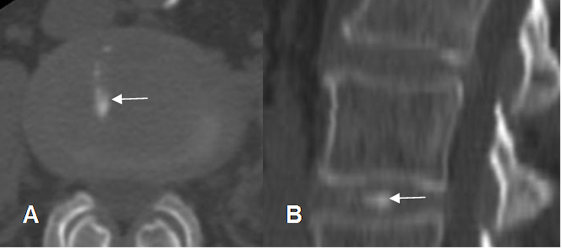

Las calcificaciones del disco son densas en Rx y TAC. Dependiendo del tipo y concentración de calcio, en algunos casos las calcificaciones se identifican como zonas con aumento de la señal en T1. (4). (Fig 36, 37 y 38).

Fig 36. Calcificación del disco.

Rx lateral. Calcificación del disco, por proceso degenerativo.

Fig 37. Calcificación del disco.

A: TAC axial y B: TAC reconstrucción sagital. Calcificación alargada, en la parte derecha del disco.

Fig 38. Calcificación del disco.

A: Rx lateral y B: TAC axial. Calcificación en el borde posterior del disco.